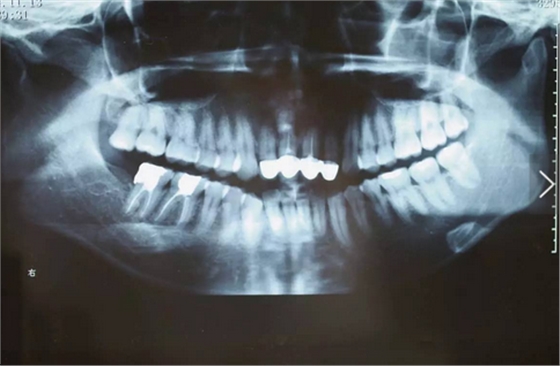

臨床檢查可見12~22烤瓷聯(lián)冠修復(fù),冠邊緣不密合,齦緣外形不協(xié)調(diào),牙齦紅腫,22烤瓷冠崩瓷。根管治療不完善,牙齦根尖部位有瘺管,X線影像顯示11、21根尖有陰影。上頜前突,上前牙修復(fù)體舌傾。 患者治療前口內(nèi)像 側(cè)位像 治療前曲面體層片 治療前前牙區(qū)X線片